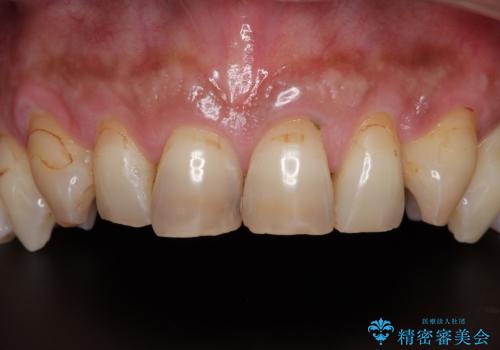

黄ばんだ前歯をきれいに 前歯の審美歯科治療

- 薬剤の影響で黄ばんでしまった前歯を気にして来院された患者様です。

お子様が大学を卒業され、経済的に余裕ができたとのことで、長年気にしていた前歯を綺麗にする決断をされたとのことでした。

奥歯の銀歯も気にはなるものの、口を開けたときに目立たないとのことで、上下ともに前歯を中心にオールセラミッククラウンにて補綴治療を行うこととしました。